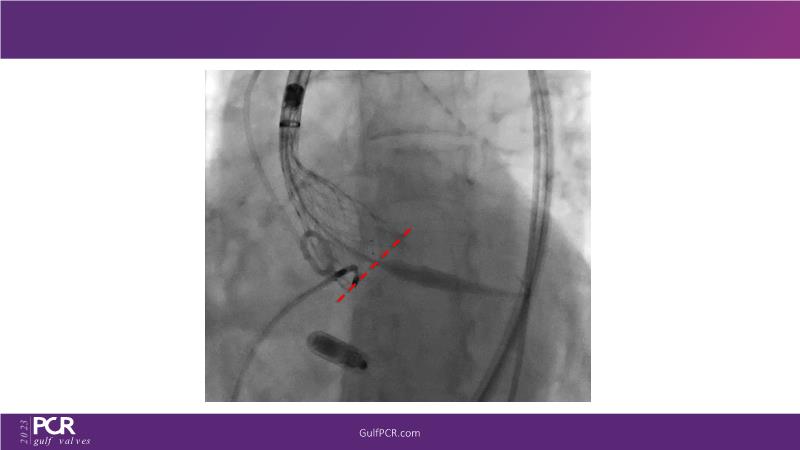

The primary focus of this GulfPCR-GIM 2023 session revolves around pre-procedural planning considerations, valve selection, and managing complex anatomies using both traditional self-expanding valves and the Evolut FX system. Additionally, the session aims to explore the work-up protocol for patients grappling with severe AS and advanced CKD, elucidate the algorithm for selecting the appropriate TAVR platform, discuss strategies to reduce contrast utilization, and highlight the distinctive advantages offered by the Evolut FX system.

• To learn more about optimization of valve deployment